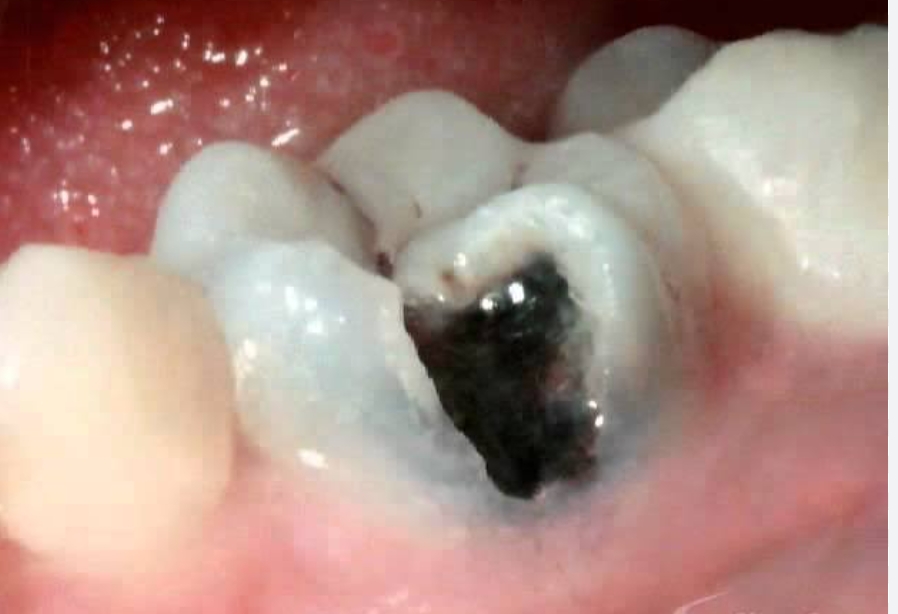

4. Stage Four: Pulp Damage – The Toothache Turns Intense

The pulp is the innermost part of your tooth and contains nerves, blood vessels, and connective tissues. When decay reaches this stage, the infection irritates and inflames the pulp, leading to severe pain.

Pulp damage means your tooth is infected from the inside. At this point, a simple filling won’t help. The typical treatment is a root canal, where the dentist removes the infected pulp, cleans the root canals, and seals the tooth. In some cases, if the damage is too extensive, the tooth may need extraction.